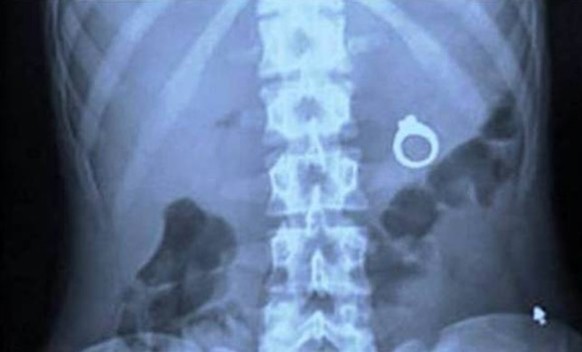

Die Operation lief scheinbar nicht wie gewünscht.